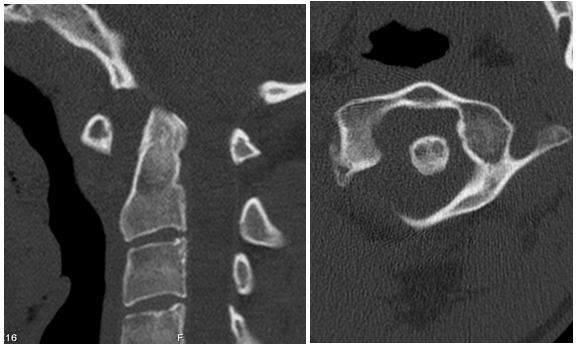

A 27-year-old male patient with no relevant medical or surgical history and working in the military army, was observed in an Orthopedics consultation, referred from primary health care for complaints of neck pain, without irradiation to the upper limbs, associated with limitation of mobility, especially in sagittal plane movements, with 4 months of evolution (Neck Disability Index (NDI) of 26). The patient denied a history of trauma, but reported upper respiratory infection (pharyngitis) one month before the onset of cervical pain. Physical examination revealed decreased cervical mobility, without other major findings. The diagnostic study began with two-plane cervical radiography (Figure 1), with an approximate ADI value of 10.5 mm, as well as dynamic radiographs (Figure 2), which demonstrated C1-C2 dynamic instability (ADI of 10.9 and 9.8 mm respectively). The CT study confirmed atlanto-axial sub dislocation and excluded the presence of fractures or facet subluxations (Figure 3). The study was complemented by magnetic resonance imaging, which confirmed atlanto-axial sub dislocation, associated with inflammation and thickening of the paravertebral soft tissues, with transverse ligament incompetence (Figure 4 - magnetic resonance imaging). Due to the decreased mobility of the upper cervical spine, the possibility of Meningitis was raised. Blood analytical study showed marginal elevation of C-Reactive Protein (28 mg/L), thus, the hypothesis of Grisel's Syndrome was placed. The patient was initially treated with the use of a Minerva cervical collar and broad-spectrum empirical antibiotic therapy with Ceftriaxone for 6 weeks, but after this period, there was unfavorable clinical evolution, with worsening of cervical pain and functional status (NDI of 30). Surgical treatment was therefore elected, through posterior atlanto-axial fixation, which is in accordance with other cases published in the literature.2The surgery was uneventful and the patient had a favorable clinical course, with significant improvement in neck pain and joint mobility, with an improvement in the NDI from 30 to 5. Radio graphically, a reduction in atlanto-axial subluxation was confirmed (Figure 5), which remained stable until 5 years of follow-up. There were no late complications and the patient resumed his normal activities.

Figure 3  TC image with C1-C2 dislocation.